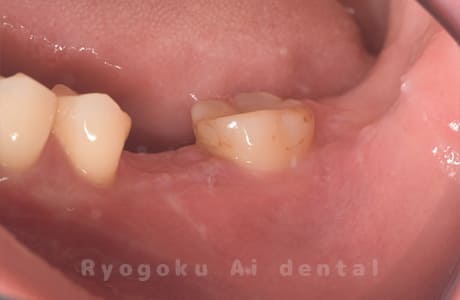

Case07

-

- 原因

- 右下6番歯根破折

- 治療内容

- インプラント治療

- 治療費用

- 約600,000円

右下の腫れが治らないとの事でご来院された患者様です。歯が割れていたため、抜歯を行い、骨に代わるお薬を入れ、インプラントを埋入致しました。経過良好で大変満足していただけました。

<リスク・副作用>

治療後、痛みや違和感、出血、腫れなどが出る事があります。喫煙者、糖尿病などの方の場合、歯が生着しない場合があります。